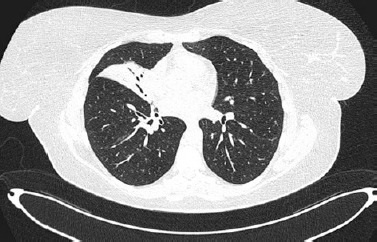

A 45-year-old female with hypothyroidism and impaired glucose tolerance was admitted to the Emergency Department (ED) because of fever, productive cough, sore throat and mucosal changes: oral erosions and conjunctivitis. Two days prior to the visit to the ED the patient was diagnosed with atypical pneumonia by a general practitioner; lately her daughter had Mycoplasma pneumoniae infection. The patient had been treated with clarithromycin 500 mg/12 h for 2 days. She reported that she had been using ibuprofen for 5 days prior to antibiotic therapy. She had never noticed any adverse reactions to ibuprofen or any non-steroidal anti-inflammatory drugs before. During the visit to the ED she was consulted by an infectious disease specialist, who confirmed mycoplasma infection with mucosal involvement. Chest high-resolution computed tomography (HRCT) revealed consolidations mainly in the middle lobe, with surrounding ground glass opacities. Continuation of antibiotic therapy and moisturizing eye drops were recommended. Six days later the patient was readmitted to the ED due to progression of mucosal changes: hemorrhagic crusting of the lips and vast erosions of the oral cavity – vestibule, tongue and palate (Figure 1). Moreover, severe conjunctivitis (Figure 2) accompanied by purulent secretion, and a cough with green sputum. Additionally, singular (below 1% of the skin body surface area) flat and red lesions (about 0.5 cm in diameter) were observed on the left thigh, right scapula, and left breast with negative Nikolsky’s sign. On physical examination, auscultation revealed crackles over the middle lobe of the right lung. Chest HRCT showed atelectasis (Figure 3) of the middle lobe and evolution of ground glass opacities in both lungs. Following a dermatological consultation, the patient was admitted to the Clinical Department of Pulmonology, Allergology and Internal Medicine with Mycoplasma pneumoniae pneumonia with a suspicion of Stevens-Johnson syndrome (SJS). On admission she was in stable medical condition, with blood pressure of 140/94 mm Hg, oxygen saturation on atmospheric air (SpO2) of 94%, regular heart rate of 96/min. Laboratory blood tests revealed high C-reactive protein (CRP) – 100 mg/l and hypokalemia. Because hypersensitivity reaction to clarithromycin could not be excluded it was replaced by doxycycline. The patient was consulted with a dermatologist, ophthalmologist and laryngologist. According to recommendations, a corticosteroid intravenous therapy was started at a dose of 60 mg methylprednisolone for 4 days, followed by gradual tapering of the dose. Ocular ofloxacin and dexamethasone were started as well as moisturizing eye drops. Moisturizing of the lips was recommended, and betamethasone with fusidic acid ointment was prescribed for application to the lips once daily. The patient was instructed to rinse the oral cavity 2–3 times daily with a formula containing nystatin, vitamin B12, borax, and anaesthesin. During hospitalization, a single intravenous infusion of 10 g immunoglobulins was administered. Positive anti-Mycoplasma pneumoniae antibodies (IgM and IgG) confirmed Mycoplasma pneumoniae infection, therefore doxycycline antibiotic therapy was continued. Following the treatment, inflammatory markers continued to decrease, and gradual improvement in mucosal lesions was observed, including the reduction of erosions in the oral cavity. The patient was discharged with the recommendation for continuing the oral steroid therapy with methylprednisolone in a gradually tapered dose over following weeks along with fluconazole and local treatment. At the follow-up visit, the patient reported significant improvement in both skin and mucosal lesions. No lesions were observed in the oral cavity or on the vermilion border of the lips, though mild tingling sensation around the lips persisted. The patient also noted persistent dryness at the outer corners of her eyes but no purulent lesions. Additionally, she reported insomnia and excessive sweating, likely related to the prolonged corticosteroid therapy. Laboratory findings showed neutrophilic leukocytosis with negative CRP, likely a side effect of systemic steroid therapy. Chest HRCT showed significant regression of inflammatory changes, with only residual postinflammatory changes in the middle lobe of the right lung. The patient’s condition has improved markedly and further reduction of the methylprednisolone dose was ordered.